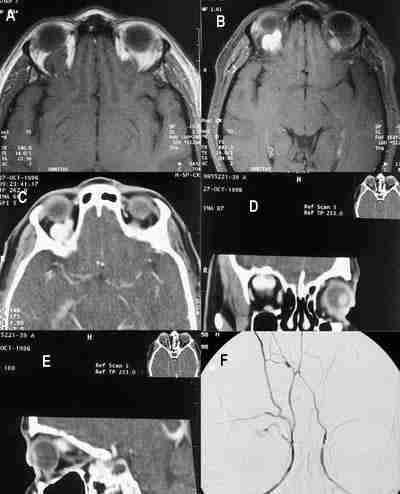

Pero es, sobre todo, en el campo de la tomografía computada (TC) y resonancia magnética (RM), donde se han producido los cambios más significativos, que han permitido al neurorradiólogo, no sólo mejorar su capacidad diagnóstica, sino aportar información de gran ayuda en la planificación de cirugías complejas e incluso al mismo acto quirúrgico. Desde que en 1972 Hounsfield realizara el primer estudio cerebral con un tomógrafo experimental a la actualidad, la evolución de la TC ha sido vertiginosa. El último gran avance en este campo, la TC helicoidal ha dado una nueva dimensión a esta técnica. Combinando el movimiento de rotación del tubo y el de traslación de la mesa a través del mismo, se crea un movimiento en hélice o espiral que permite una adquisición volumétrica de datos similar a la que se realiza en RM. Esto consigue, por una parte, disminuir de forma muy importante los tiempos de exploración (30 segundos para la realización del estudio completo) y la dosis de radiación y, por otra, hacer reconstrucciones en distintos planos con sólo una mínima pérdida de calidad respecto a la proyección basal (figura 1).

53-01.jpg (20780 bytes)

Figuras 1a, b, c, d, e y f. Imagen axial (a) en técnica espiral con reconstrucciones biplanares coronal (b), y de superficie de estructuras óseas (c, d, e) y de piel (f). Se observa fractura de la lámina papirácea (a) con hundimiento del suelo (b) y con esquirla ósea. En las reconstrucciones tridimensionales de superficie puede valorarse su repercusión estética.

Si la placa simple es patológica o dudosa, se debe recurrir siempre a hacer una TC que ha revolucionado el diagnóstico de estos traumatismos porque delimita bien las lesiones óseas pero, además, permite ver las partes blandas orbitarias y su relación con los senos paranasales, especialmente útil en las fracturas de la pared medial (figura 1). Con la nueva generación de TC helicoidal se pueden hacer adquisiciones de cortes muy finos en tiempos muy cortos que permite hacer reconstrucciones sagitales, coronales y 3D sin necesidad de movilizar al paciente (figura 1). En nuestra experiencia la calidad de las reconstrucciones, a pesar de ser aceptable no se puede comparar con las adquisiciones directas y sólo sirven para descartar lineas de fractura evidentes o luxaciones pero no tienen nitidez para valoración fina de lesiones pequeñas, por lo tanto siempre que las condiciones del enfermo lo permitan, haremos adquisiciones directas (figura 13) y en caso contrario recurriremos a las reconstrucciones. Con la TC se ve el contenido orbitario herniado en el seno maxilar (grasa o músculo) y esto nos permite anticiparnos a las complicaciones como enoftalmos o diplopía. Con la TC se pueden valorar simultáneamente las lesiones asociadas intracraneales o faciales (26).